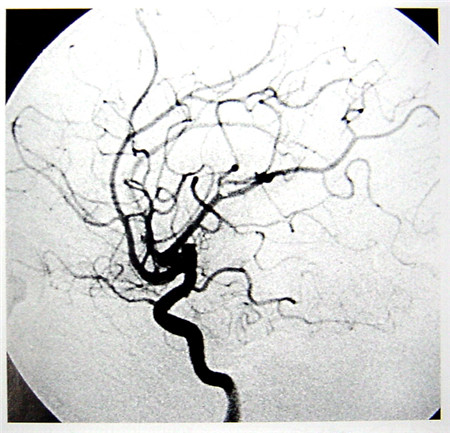

數字減影血管造影技術(Digital Subtraction Angiography,DSA)是一種新的X線成像系統,是常規血管造影術和電子計算機圖像處理技術相結合的產物。DSA的成像基本原理是將受檢部位沒有注入造影劑和注入造影劑后的血管造影X線熒光圖像,分別經影像增強器增益后,再用高分辨率的電視攝像管掃描,將圖像分割成許多的小方格,做成矩陣化,形成由小方格中的像素所組成的視頻圖像,經對數增幅和模/數轉換為不同數值的數字,形成數字圖像并分別存儲起來,然后輸入電子計算機處理并將兩幅圖像的數字信息相減,獲得的不同數值的差值信號,再經對比度增強和數/模轉換成普通的模擬信號,獲得了去除骨骼、肌肉和其它軟組織,只留下單純血管影像的減影圖像,通過顯示器顯示出來。通過DSA處理的圖像,使血管的影像更為清晰,在進行介入手術時更為安全。

超聲經顱多普勒血流分析儀(TCD)提供的是實時動態的腦血管的血流動力學資料。核磁共振血管成像(MRI)提供的是大腦實質細胞的損壞與形態學上改變的影像學資料 。數字減影血管造影(DSA)提供的是腦血管瞬間形態學上的變化,且有創傷。

數字減影血管造影DSA腦血管圖像顯示                                                      核磁共振MRI掃描腦組織圖像